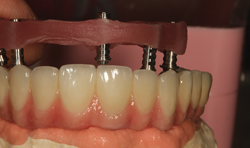

Fig. 13 Internal implant screws

We can see the internal implant screws in the next mirrored image (Fig. 13), not previously visible.